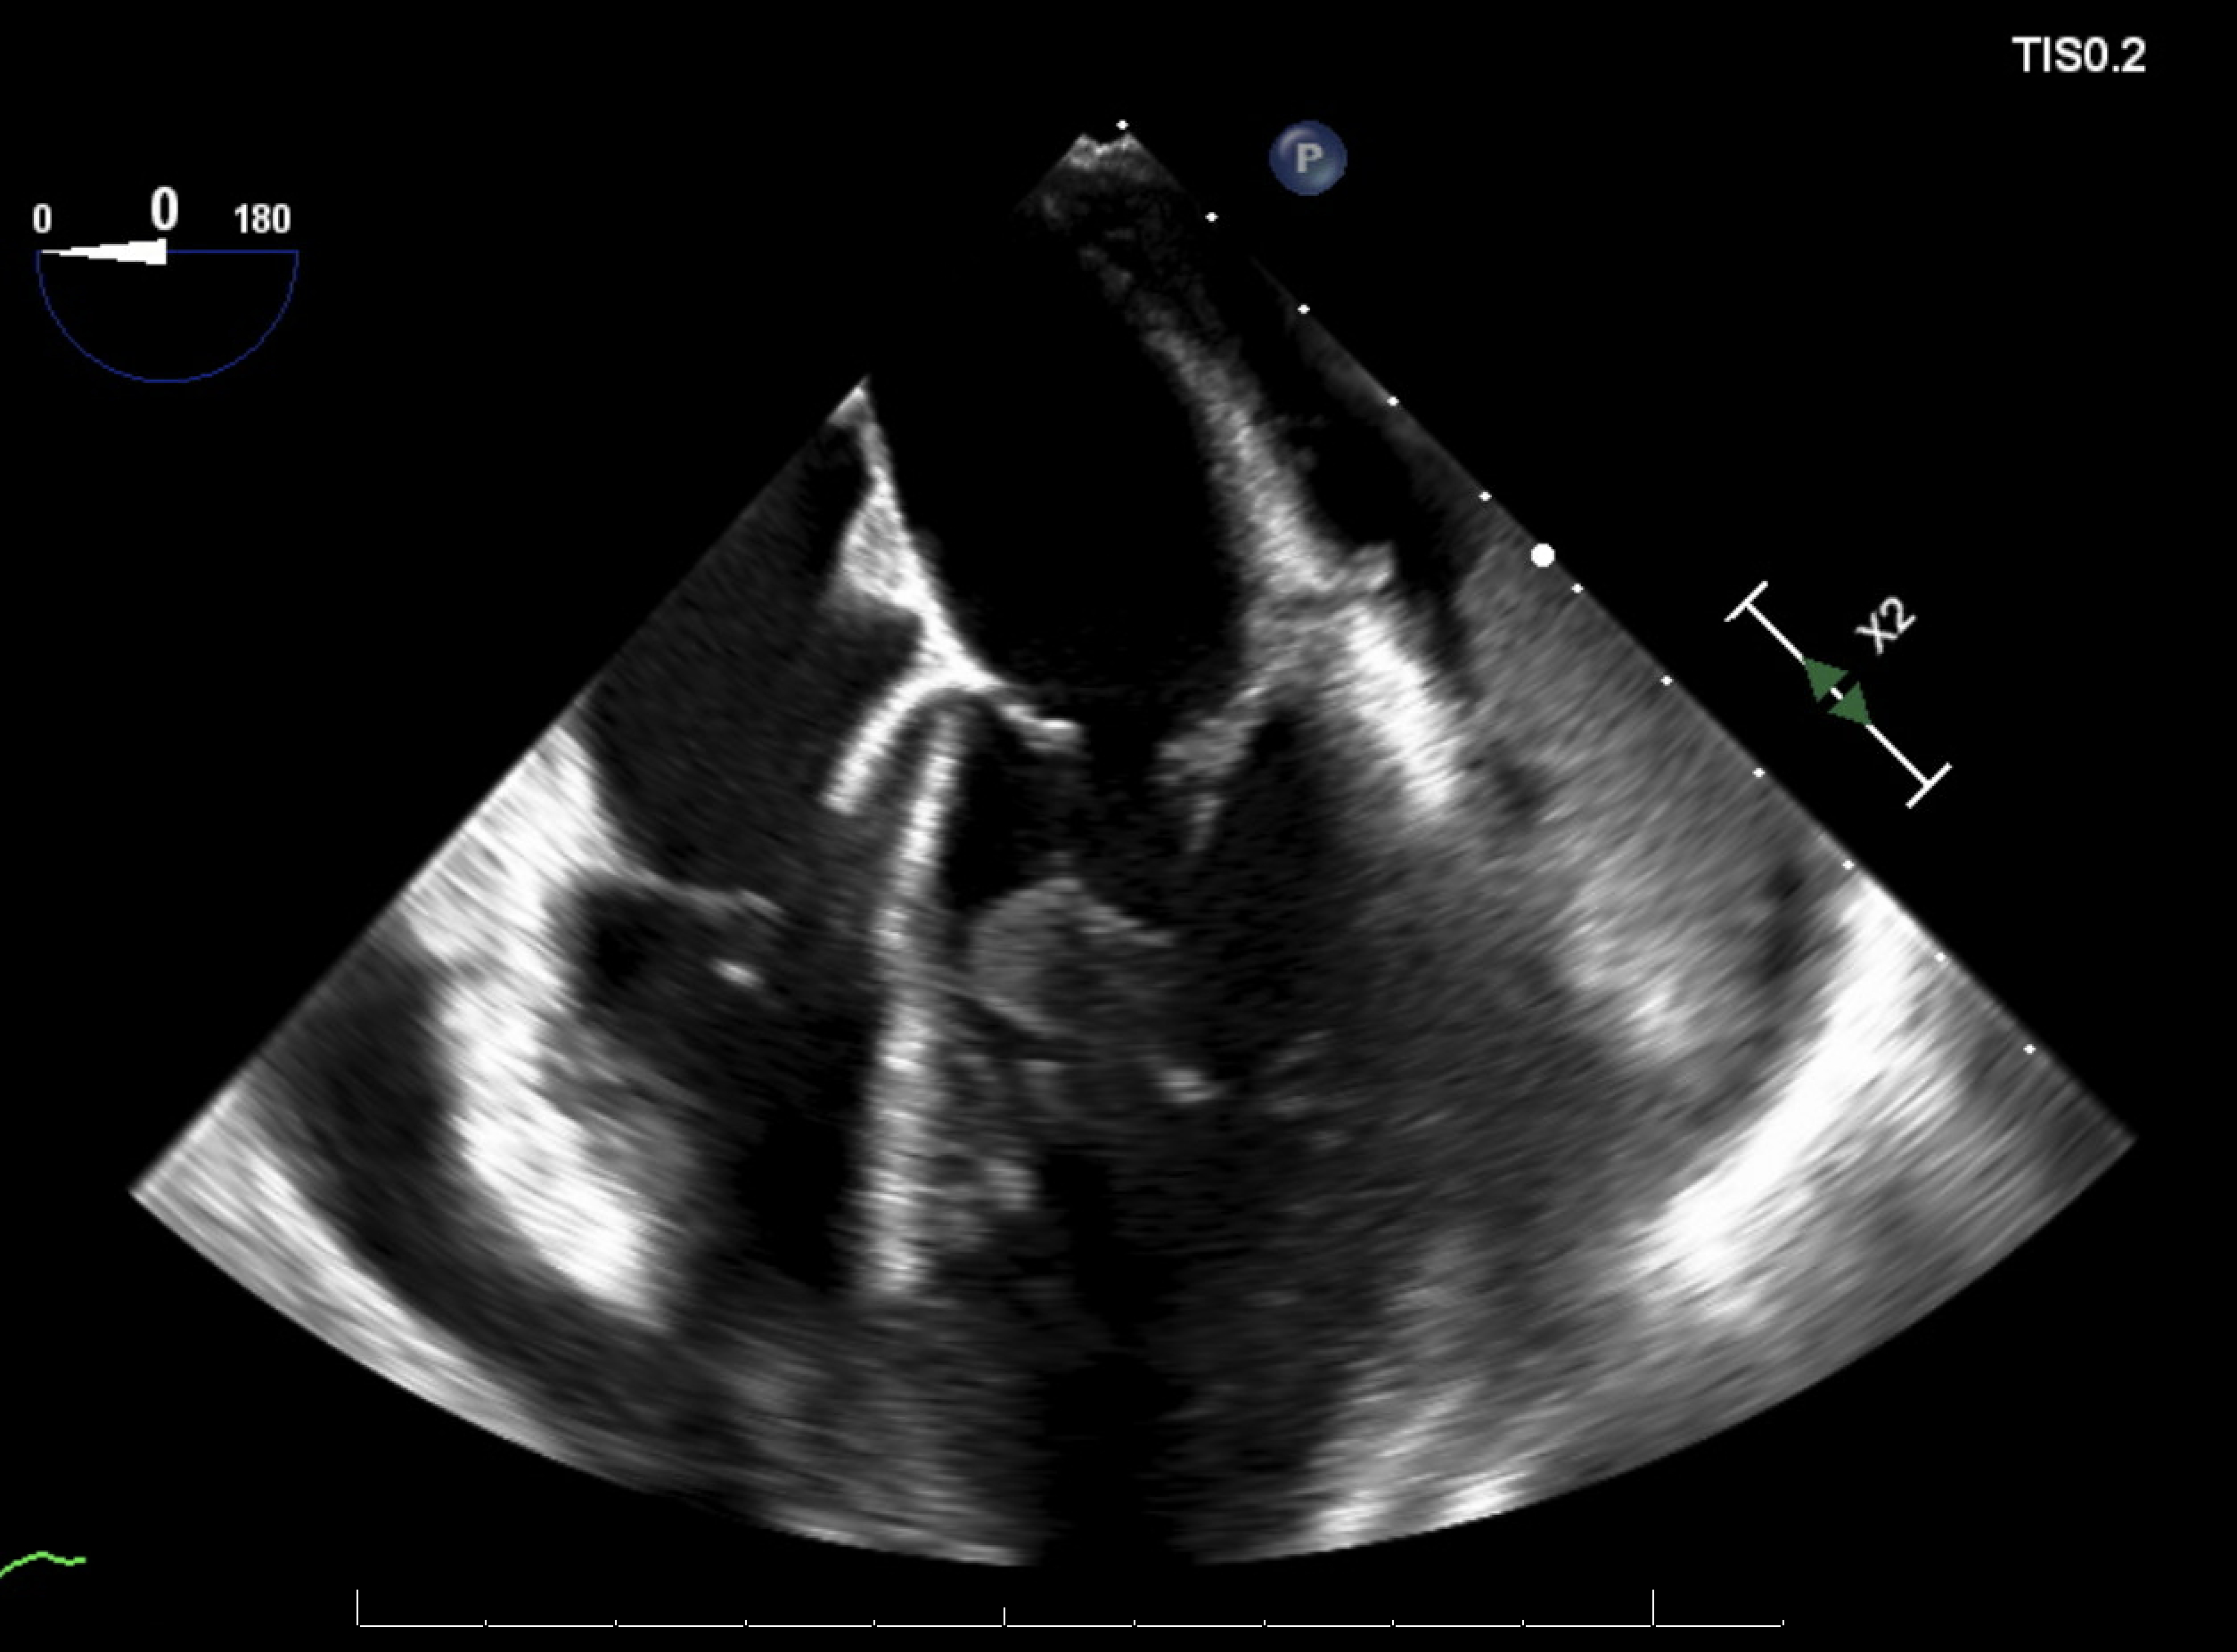

Due to persistent bacteremia and worsening hemodynamics, a repeat TEE was performed, which revealed a new, large circumferential pericardial effusion with right atrial systolic collapse, right ventricular diastolic collapse, plethoric IVC, a 1.4 × 0.8 cm highly mobile vegetation on the mitral valve subvalvular apparatus, and multiple large echogenic structures in the pericardial space concerning for vegetation. Pericardiocentesis revealed a purulent, MRSA-positive fluid, confirming purulent pericarditis. The antibiotics regimen was intensified and the patient was transferred to a higher level of care facility for cardiac surgery evaluation.